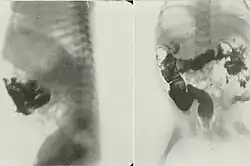

Patent omphalomesenteric duct.

Omphalomesenteric duct cysts (ODC), also known as an omphalomesenteric duct remnant or vitelline cyst, are developmental defects relating to the closure of the omphalomesenteric duct. It usually disintegrates within six weeks of gestation, but remnants of the cyst can sometimes be found along the intestines or umbilicus. Any remnants can be removed via surgical means.[1]